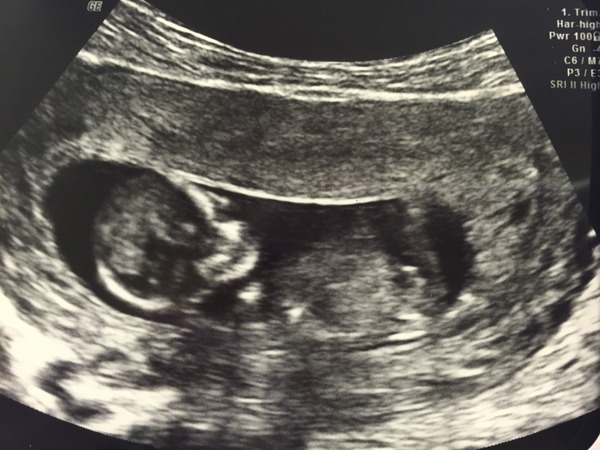

My 12wk scan was yesterday (but I was 10+5), they put me a day back again so new due date is 15th May. Pictures were very fuzzy so not great but we did see more on the screen itself; baby was moving around a lot, very active and heart beating away. It was a big difference from our 9 wk scan as could see the head/body/hands/legs etc so was lovely but feel if it had been a couple of wks on we would have seen more and got better pics. But our main concern was that baby is well and it was :)

Mama were you offered a re-scan? At my scan last week it was too early for the nuchal testing (11 weeks) so I had another scan yesterday. The put my EDD back another day to May 5th. Picture wasn't so good as I completely forgot to go with a full bladder, but at least it doesn't look like my baby is smoking/waving a gun in this one!